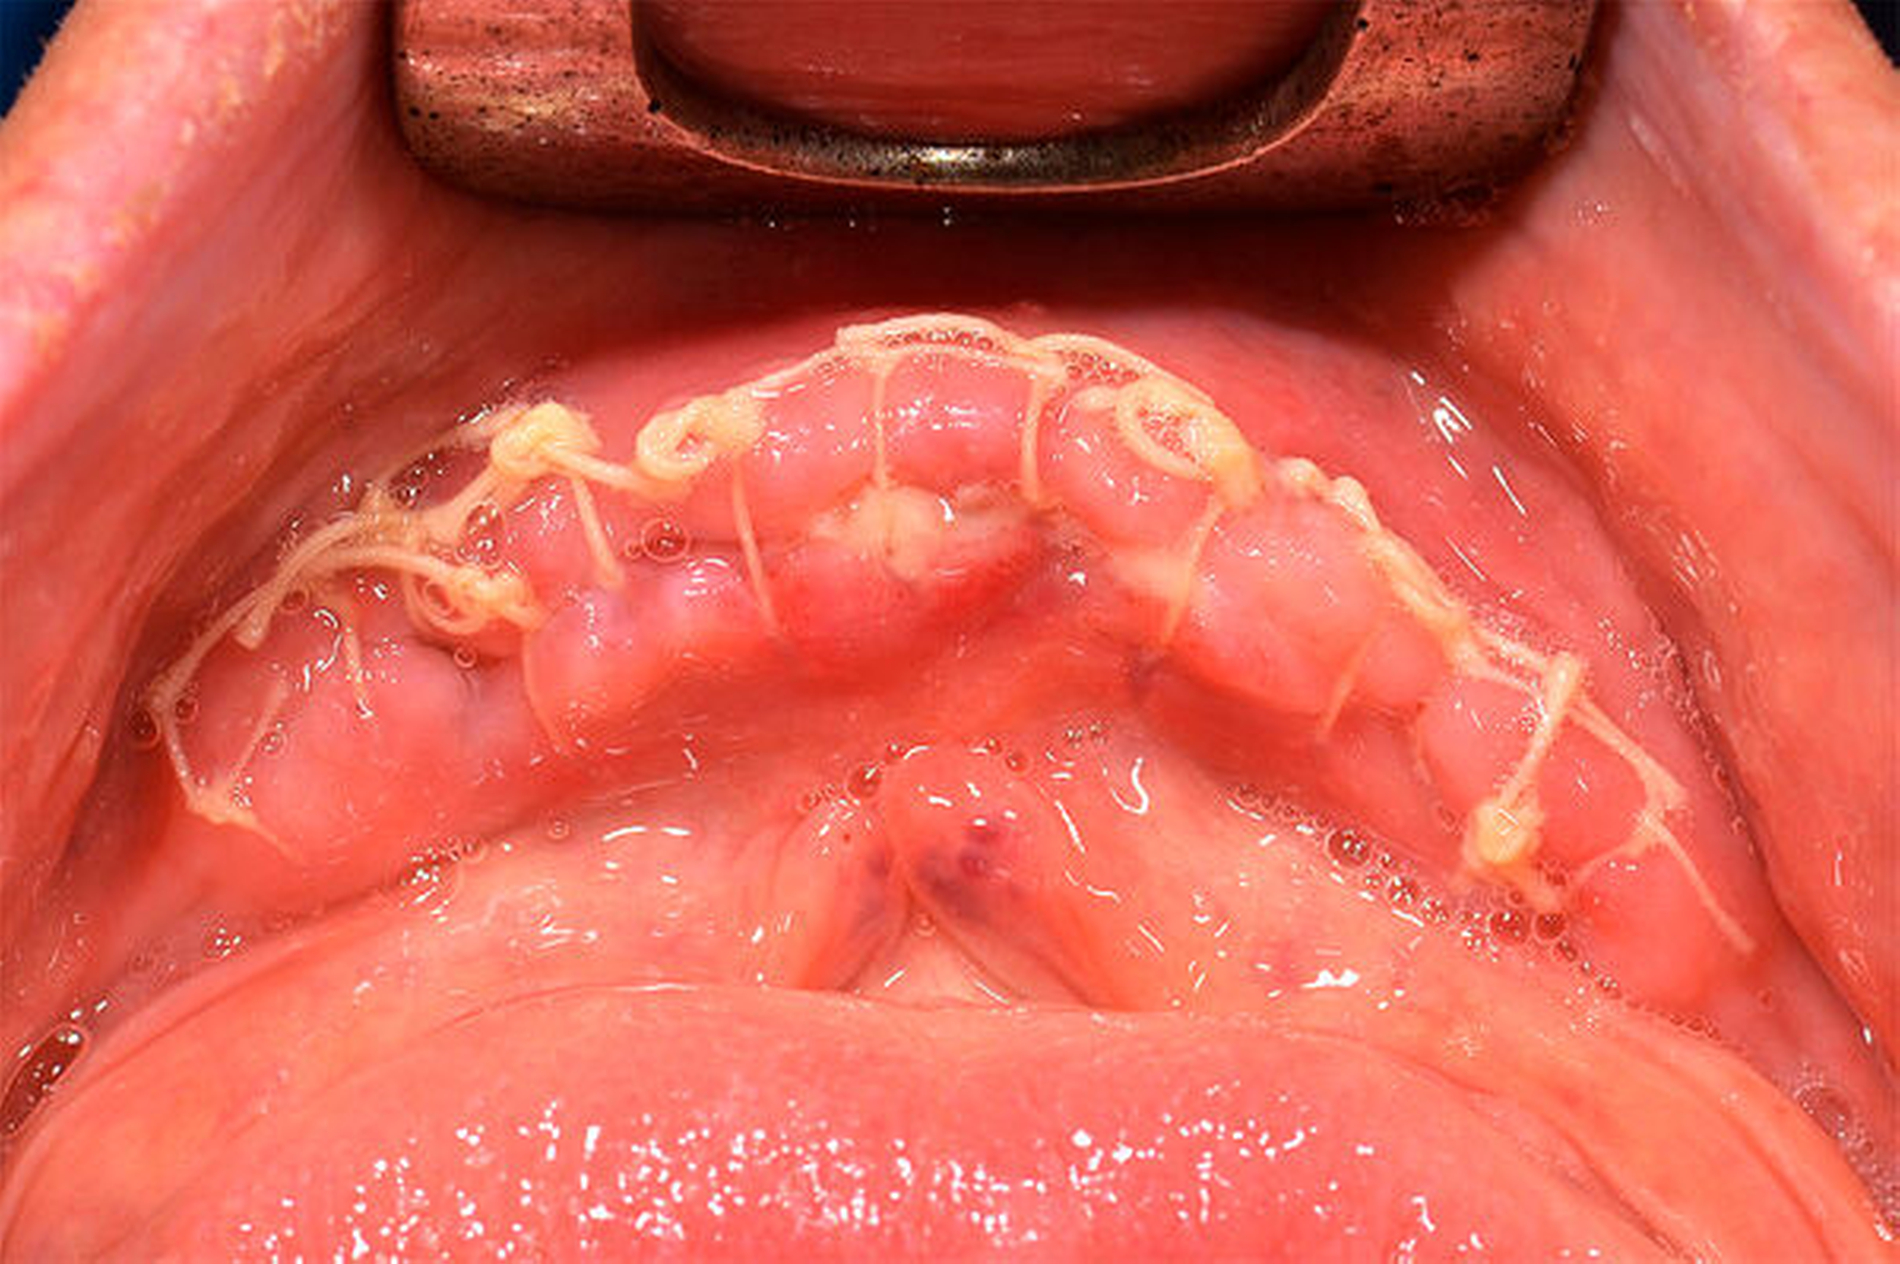

Postoperativ wurde das Substitutionsschema für acht Tage laut Plan fortgeführt. Neben der bedarfsgerechten Analgesie mit Paracetamol 3 x 3 g i. v./d (Perfalgan®, BMS, München) wurde die Antibiose prolongiert fortgesetzt. Hierunter zeigte sich der weitere stationäre Aufenthalt unauffällig, so dass der Patient bei zeitgerechtem Lokalbefund nach Beendigung der Substitution in die Häuslichkeit entlassen werden konnte (Abbildung 3). Über das postoperative Verhalten und die weitere ambulante Nachsorge wurde der Patient vor der Entlassung ausführlich unterrichtet.